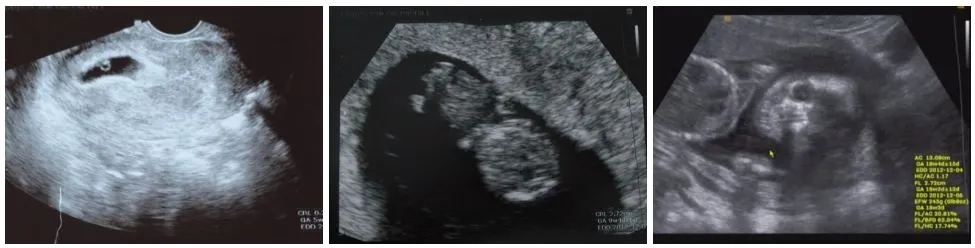

올챙이 알 같던 모습이 젤리 곰이 되고, 해골이 되고, 갈수록 거세지는 태동을 느끼면서 ‘우리 아이’라는 애틋함이 생기기 시작했어요. 아직도 내가 정말 엄마가 되는 건가, 이 사람이 아빠가 되는 건가 분명하게 실감이 나지는 않았지만, 아련한 기대와 설렘에 두근거림을 느낄 수 있었습니다.